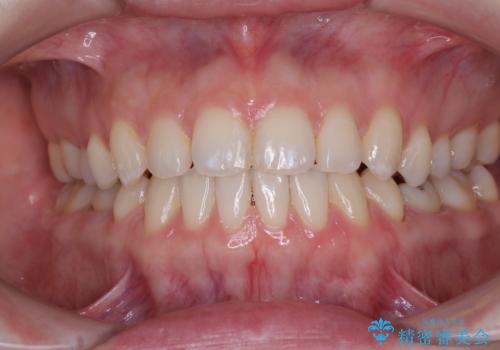

すきっ歯をインビザラインできれいな歯並びに改善

- 前歯の隙間を気にして来院された患者様です。

隙間や叢生の程度はそれほど著しいものではなかったので、インビザラインでもワイヤー矯正でも対応可能でしたが、極力目立たない装置を希望されたため、インビザラインにて矯正治療を行うこととしました。

すきっ歯の原因は色々ありますが、嚥下や発音時の舌突出癖が大きな原因となることがあります。

こちらの患者様も強い突出癖があったため、舌のトレーニング指導を行いました。